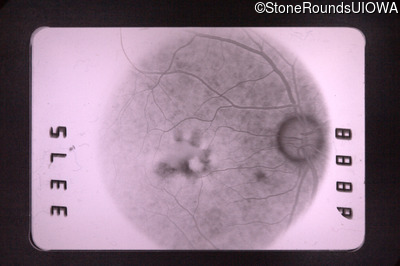

Fluorescein Angiography - Right - 20/50 +1

Exemplar